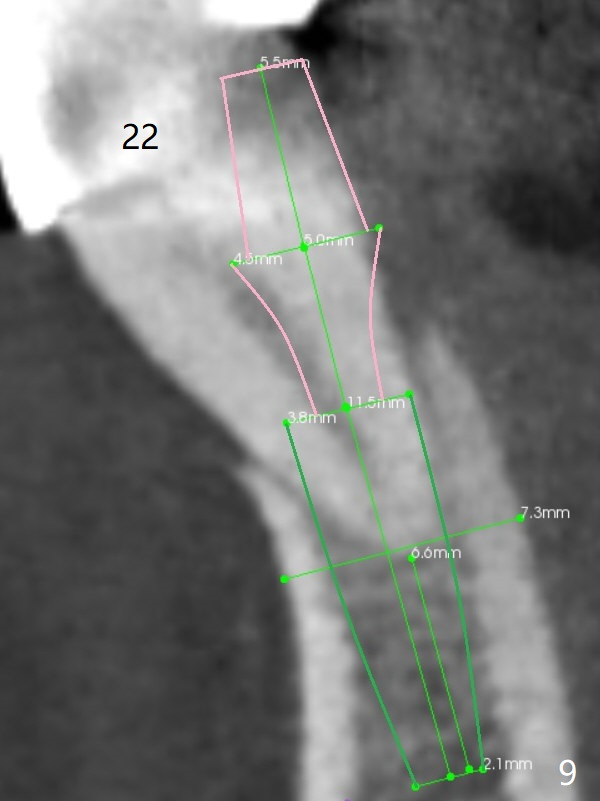

A 46-year-old man has finished upper implant placement (9-11 15 UR provisional) and wants to have lower anterior done (Long Cuff Wax up 2). The tooth #28 has exfoliated, while #22-27 FPD has mobility. It appears that the anchor tooth #22 has more severe periodontitis than that of #27. If the condition remains the same, section FPD between #22 and 23. Implants will be placed probably at #23, 26, 27 and 28. If both of the anchor teeth are non-salvageable, the possible implant will be at #22, one incisor, 27 and 28. In fact the patient requests an implant at #28.